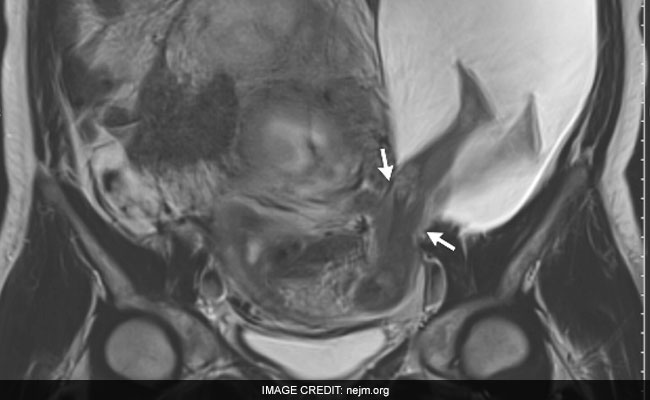

A fetus' legs protruding from the womb.

The woman's doctors scanned the rupture and fetus via MRI. Bouet and a colleague published a picture of the amniocele in the New England Journal of Medicine on Thursday. Despite appearances, a savage fetal kick was not to blame.

"The fetal legs did not cause the rupture," Bouet said. Instead, the woman's history of five C-sections likely led to a tear, in the obstetrician's view. Due to scarring from the previous births, parts of the uterus remained atypically rigid instead of enlarging during the woman's latest pregnancy. The uterine wall ruptured when it was unable to expand, causing an inch-long tear.